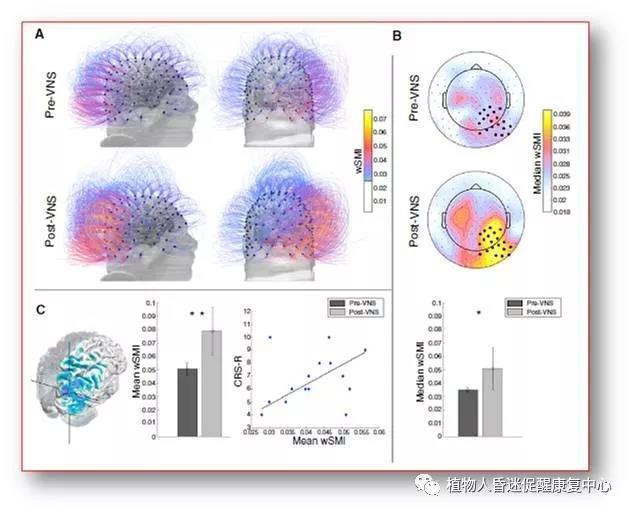

第三、迷走神经刺激(VNS): 最近法国的研究人员应用迷走神经刺激促醒了一名车祸后植物状态持续15年的35岁男子。这一结果发表在《美国当代生物学》杂志上,这一结果对人们普遍认为植物状态持续超过12个月就是不可逆转的观念提出了质疑。

通过刺激迷走神经可能改善患者目前的生存状态。迷走神经刺激(VNS),已被用于癫痫症和抑郁症的治疗。另外迷走神经将大脑和身体的其他部位连接,其在清醒、警觉和认知等许多方面都起着重要作用。

他们选择了一例植物状态已经超过15年,没有任何好转迹象的患者来测试VNS恢复意识的能力,这样就排除了患者自身修补的能力。经过一个月的迷走神经刺激,病人的注意力、运动和大脑活动明显改善。患者开始对简单命令做出回应。例如,他可以用眼睛跟踪物体,并按要求转动头部。他的母亲说,当治疗师读书时,他能保持一定的注意力。刺激后,研究人员还观察到了病人对“威胁”的反应。例如,当研究人员的头突然靠近病人的脸时,他会睁大眼睛,反应惊讶。

研究人员认为经过VNS治疗,患者已经从多年的的植物状态,进入最小意识状态。脑电图记录了大脑在运动、感觉和意识方面的主要变化,同时显示大脑功能连接增加。PET-CT扫描显示大脑皮层和皮层下区域的代谢活动也增加。